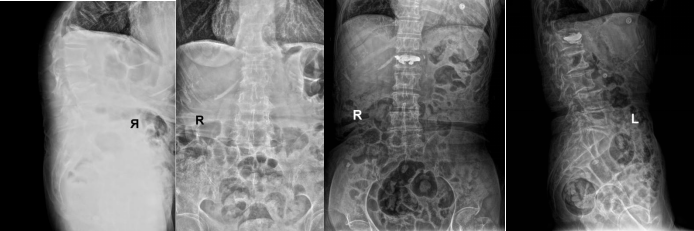

90岁单某(本院病例)L1椎体压缩性骨折案例中,团队运用5G远程会诊系统,联合内分泌科调整抗骨质疏松方案后实施椎体成形术,患者术后3日即恢复行走能力,骨密度值半年内提升12%。